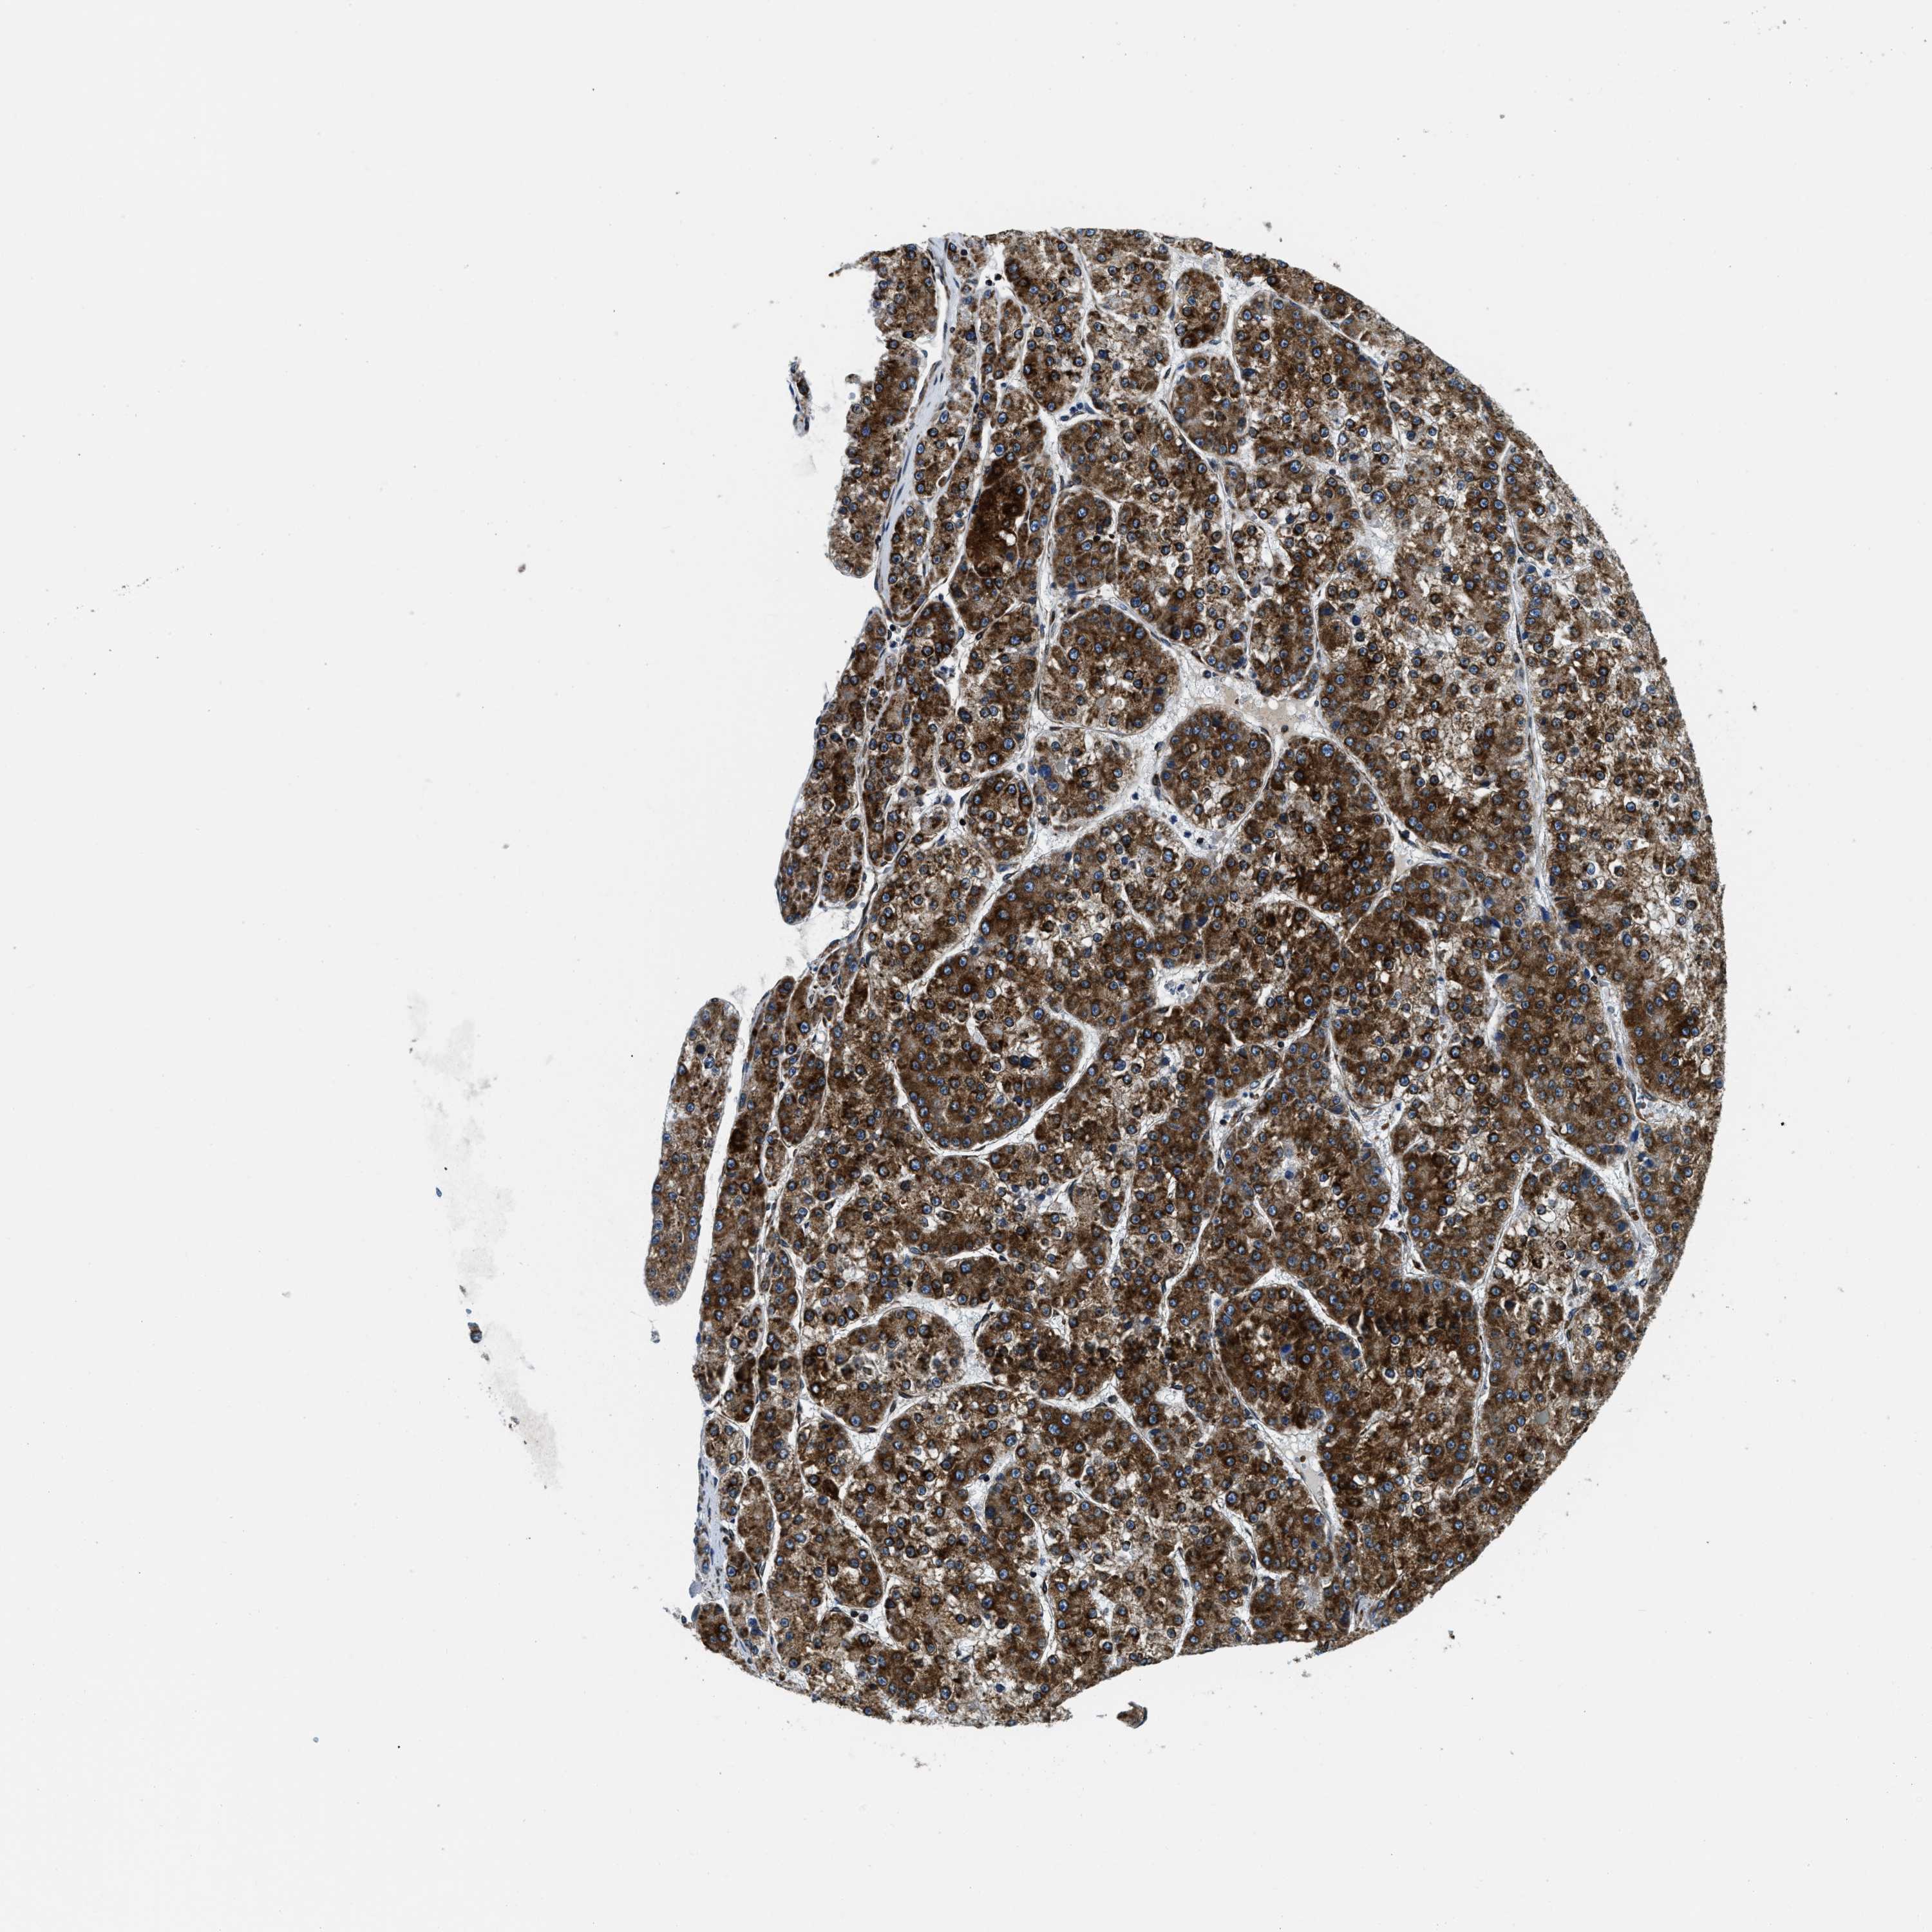

LIVER CANCER - Protein expressioni

A mouse-over function shows sample information and annotation data. Click on an image to view it in a full screen mode. Samples can be filtered based on level of antibody staining by selecting one or several of the following categories: high, medium, low and not detected. The assay and annotation is described here.

Note that samples used for immunohistochemistry by the Human Protein Atlas do not correspond to samples in the TCGA dataset.

Antibody stainingi

Antibody staining in the annotated cell types in the current human tissue is reported as not detected, low, medium, or high, based on conventional immunohistochemistry profiling in selected tissues. This score is based on the combination of the staining intensity and fraction of stained cells.

Each image is clickable and will lead to virtual microscopy that enables deeper exploration of all samples and also displays staining intensity scores, fraction scores and subcellular localization as well as patient and tissue information for each sample.

Antibody HPA019698

Staining

High

Medium

Low

Not detected

Intensity

Strong

Moderate

Weak

Negative

Quantity

>75%

75%-25%

<25%

None

Location

Nuclear

Cytoplasmic/membranous

Cytoplasmic/membranous,nuclear

Cholangiocarcinoma

Carcinoma, Hepatocellular, NOS